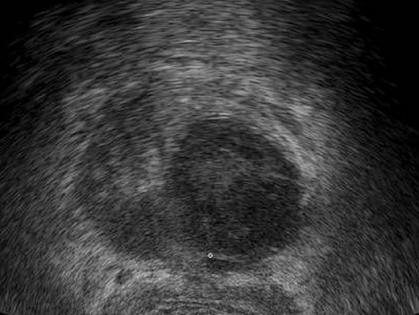

/Infekte in der AM /Harnwegsinfekte /Cystitis beim Mann /akute bakterielle Prostatitis /Prostata-Abszeß im Ultraschall Prostata-Abszeß im Ultraschallvon: Christoph FischerUS-Bild: Liquide Aussparung, im Randbereich häufig fingerartige Ausbreitung[1]